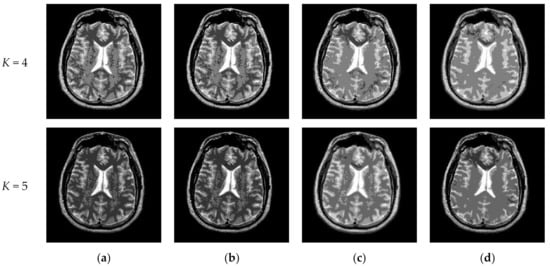

Figure 10 and Figure 11 display segmentation results of different algorithms for slice #042 and slice #082, respectively. For single level of thresholding K = 1, it can be observed that segmentation results obtained by the Otsu method have many fragmented small areas, such as the lower soft tissue in the first row of Figure 10a, whereas IIMT performs slightly better. However, the edges segmented by HL-IIMT and Proposed are much clearer. In the case of , it can be seen that Otsu and IIMT have similar segmentation effects. HL-IIMT and Proposed are better than Otsu and IIMT in terms of edge-preserving and denoising, as shown in the segmentation results in Figure 11 (K = 2, K = 4).

Figure 11.

Segmentation results obtained by different segmentation algorithms for slice #082 with number of thresholds K from 1 to 5: (a) Otsu, (b) IIMT, (c) HL-IIMT, (d) Proposed.

Table 2 shows the values of uniformity measure (U) of Proposed, HL-IIMT, IIMT, and Otsu algorithms for slice #042 and slice #082. The best evaluation results are marked in bold. It can be noted that the U values achieved by Proposed are the highest for both of the two test images. To more clearly present the results, Figure 12 illustrates the comparison of U for different algorithms based on Table 2. In Figure 12, it can be clearly noted that Proposed achieves the highest values, and HL-IIMT comes second, followed by IIMT and Otsu. This indicates that the novel thresholding method IIMT presented in this paper is effective, and our Proposed based on IIMT can obtain satisfactory segmentation results with clear edges and little noise.